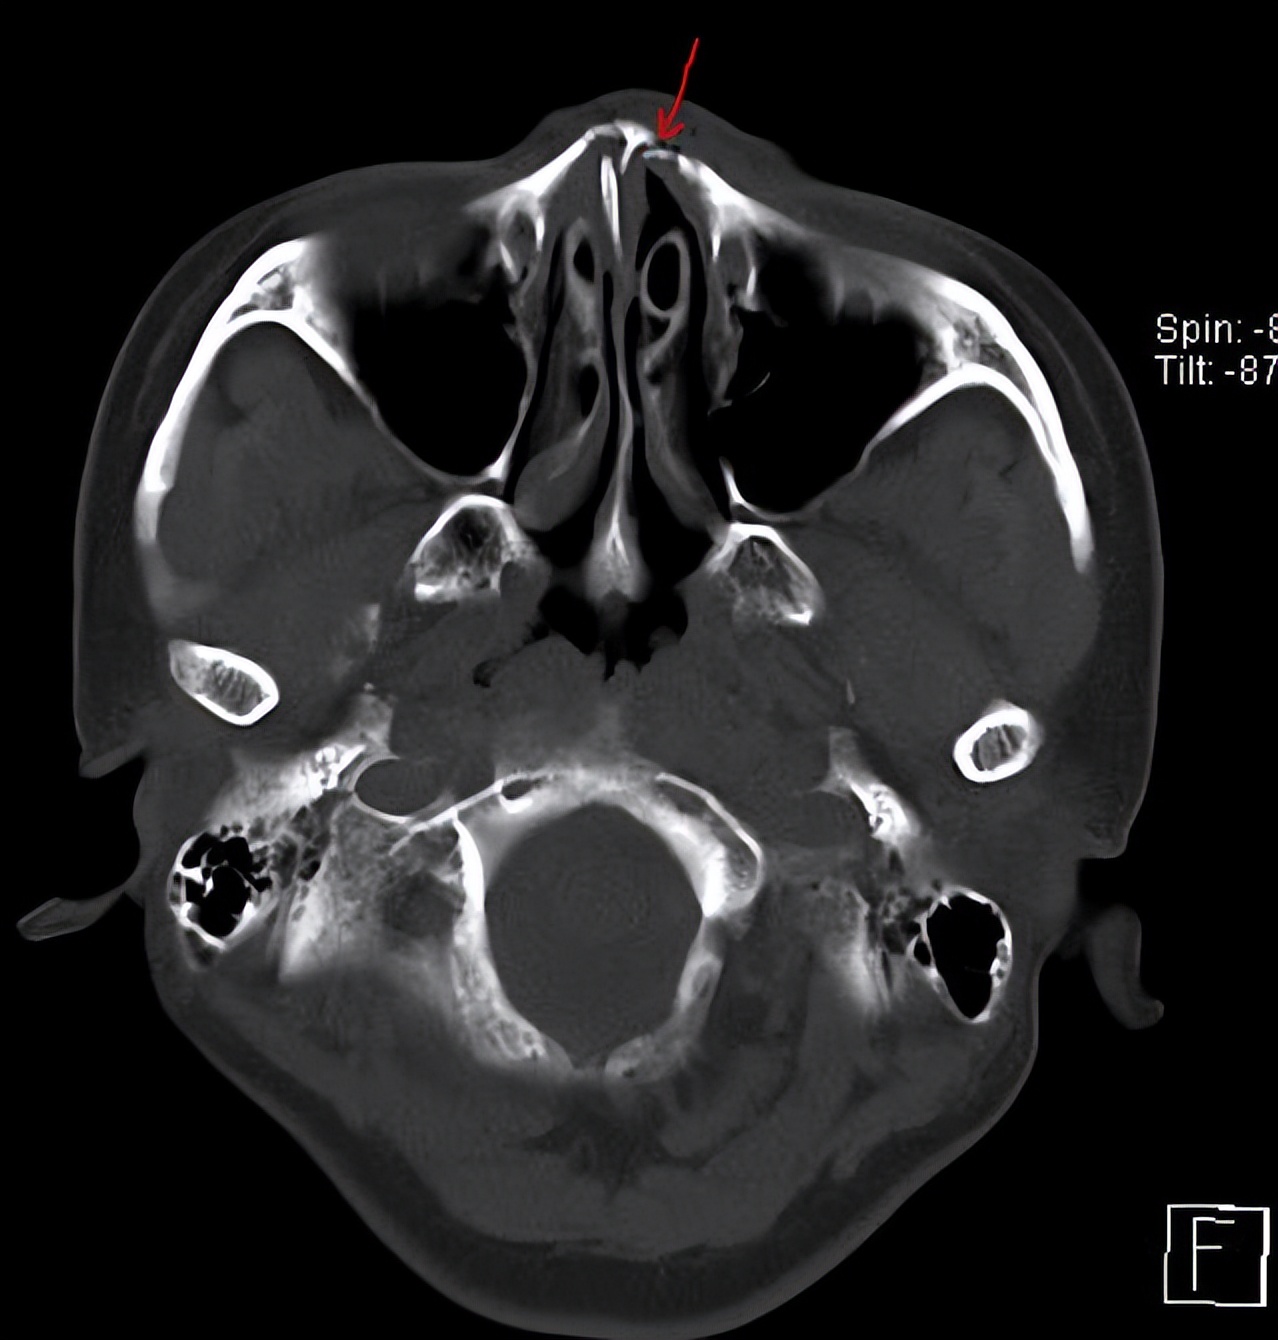

各位麻烦帮我看看这个ct片上我的这个鼻中隔偏曲算严重吗

图片尺寸1000x1333